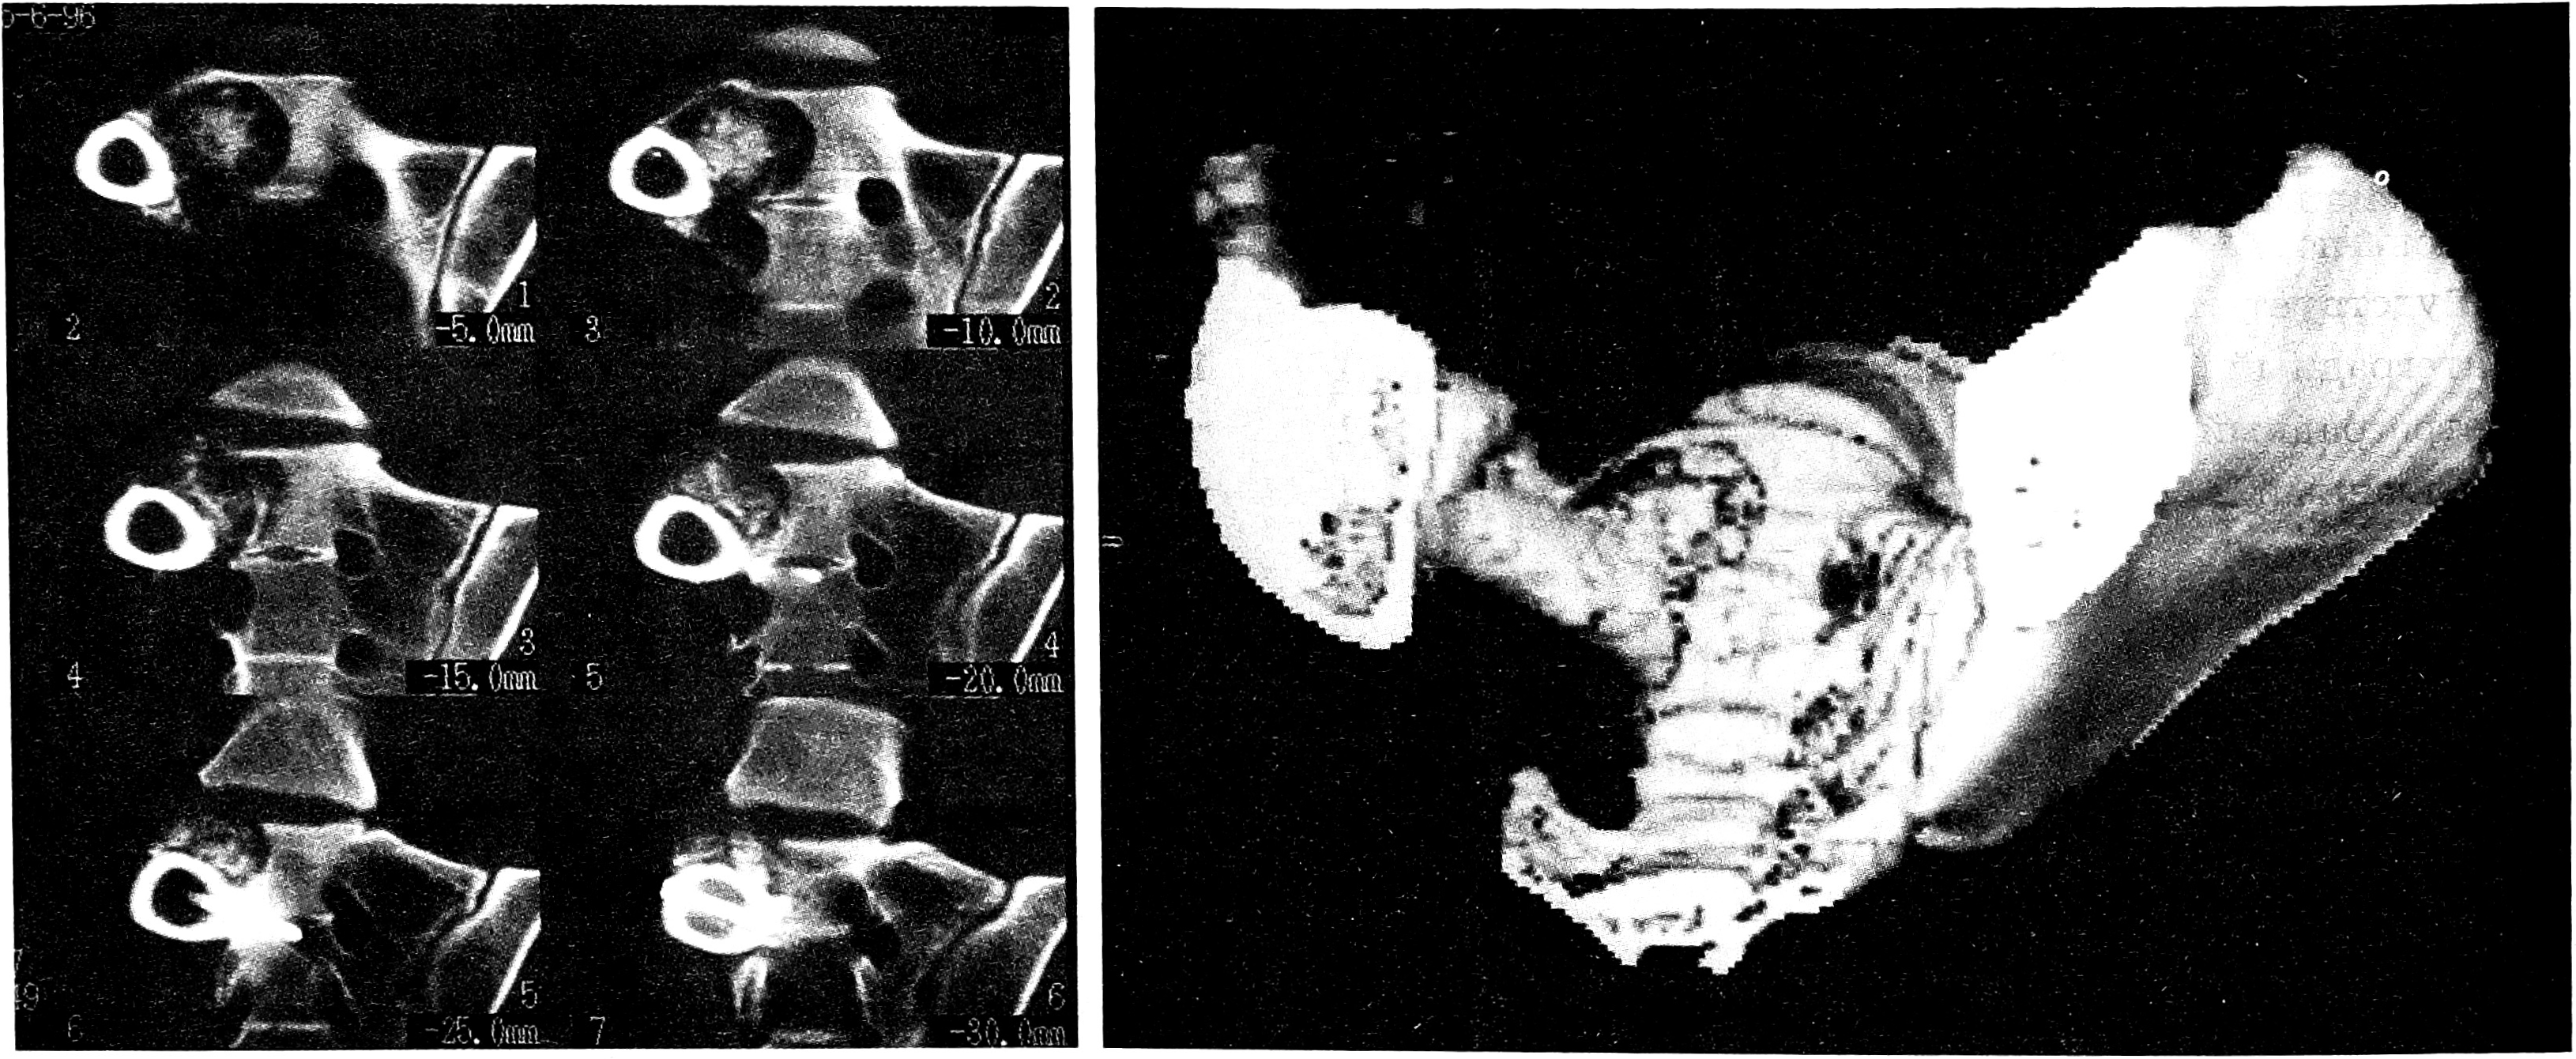

Рис. 5. Больной К., 62 лет. Диагноз: опухоль левой почки, метастатическое поражение крестца и его боковой массы справа.

а — обзорная рентгенограмма в прямой проекции: костной патологии не обнаруживается; б — МРТ: опухоль S1-S3 с поражением боковой массы крестца справа. Гетерогенный гиперинтенсивный сигнал в режиме Т2. Подозрение на опухоль левой почки; в — КТ: остеолитический очаг в телах S1-S3 и боковой массе крестца справа, контуры очага четкие; г — КТ левой почки: опухоль, занимающая всю верхнюю часть лоханки.